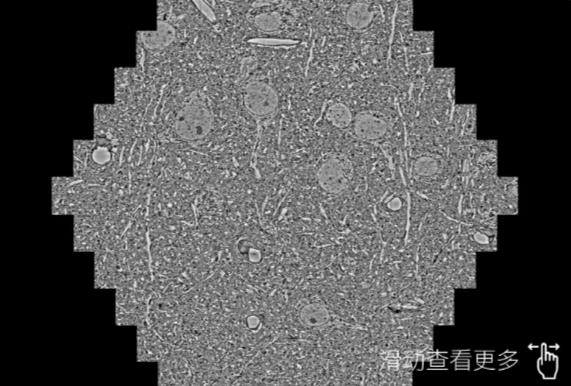

鼠脑切片。左图使用昌都蔡司昌都扫描电镜MultiSEM706对165μmx143pm面积区域成像,耗时仅需1.5秒。右图为鼠脑切片中30μm区域放大效果。样品由芝加哥大学B.Kasthuri提供。

使用蔡司高速昌都扫描电镜MultiSEM对1mm²人脑皮层组织进行高分辨成像,并对其中的各种细胞结构进行三维重构分析。左图展示了2x3mm²组织平面中锥体神经元的三维重构效果。右图显示了局部体积神经元三维重构。图像由哈佛大学chtman实验室提供,渲染图由D. Berger 制作。